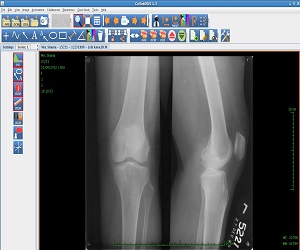

CollabDDS provides a real time collaborative environment to visualize medical (Skeletal) and dental images (digitized X-Ray images or DICOM data) for diagnosis and treatment planning. CollabDDS has various image processing tools to visualize the data and also annotate. An inbuilt repository of annotated images can be used for education. Further it enables real time collaboration for diagnosis between physician at PHC level and experts at medical colleges and hospitals. CollabDDS is unique as it allows the viewing and processing of digitized X-Rays in various standard image formats like JPEG and DICOM and also allows this data to be saved for later review/ study.

The model project “Network Enabled Medical Diagnosis and Education in Skeletal Imaging using X-Rays” funded by the National Knowledge Network (NKN), was undertaken as a Proof of Concept to provide a network based system for radiological and orthodontic diagnosis using X-Rays. The area of study being complicated required expertise in varied domains such as but not limited to Orthodontics, Orthopedics, Radiology, Computational Methods, CAD/ Rapid Prototyping, Image Processing & Pattern Recognition. Project was planned in two phases; first one being to develop an application which could enable visualization and processing of radiological data over a collaborative platform and second to effectively roll out and enhance the application as per the end user needs.

With the proof of concept having gone through successfully, a Pilot Project for Implementation of CollabDDS at Medical and Dental Colleges and Hospitals has been undertaken. This is an extension of the POC to the Operational Research Phase as a prelim to rollout. This pilot implementation is used to evaluate the efficiency and effectiveness of remote diagnosis. Further this phase also incorporates a module which carries out Cephalometric analysis for orthodontic surgeons to enable diagnosis and treatment planning of their patients. This phase would also include the Enhancement of CollabDDS and Advanced Applications on 3D imaging. It would involve the reconstruction of 3-D models from CT / Surface images, development of methodologies for orthopedic implant development using 3D models.